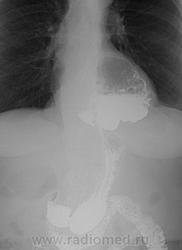

Желудок: в вертикальном положении кардиофундальный отдел расположен в средостении (фиксирован), форма не изменена, смещаемость части желудка, расположенной в брюшной полости свободная. Складки слизистой прослеживаются на всём протяжении, ровные. Перистальтика глубокая, начальная эвакуация своевременная .12-перстная кишка и начальные петли тощей кишки без особенностей.

Фиксированная параэзофагеальная кардиофундальная грыжа пищеводного отверстия диафрагмы.